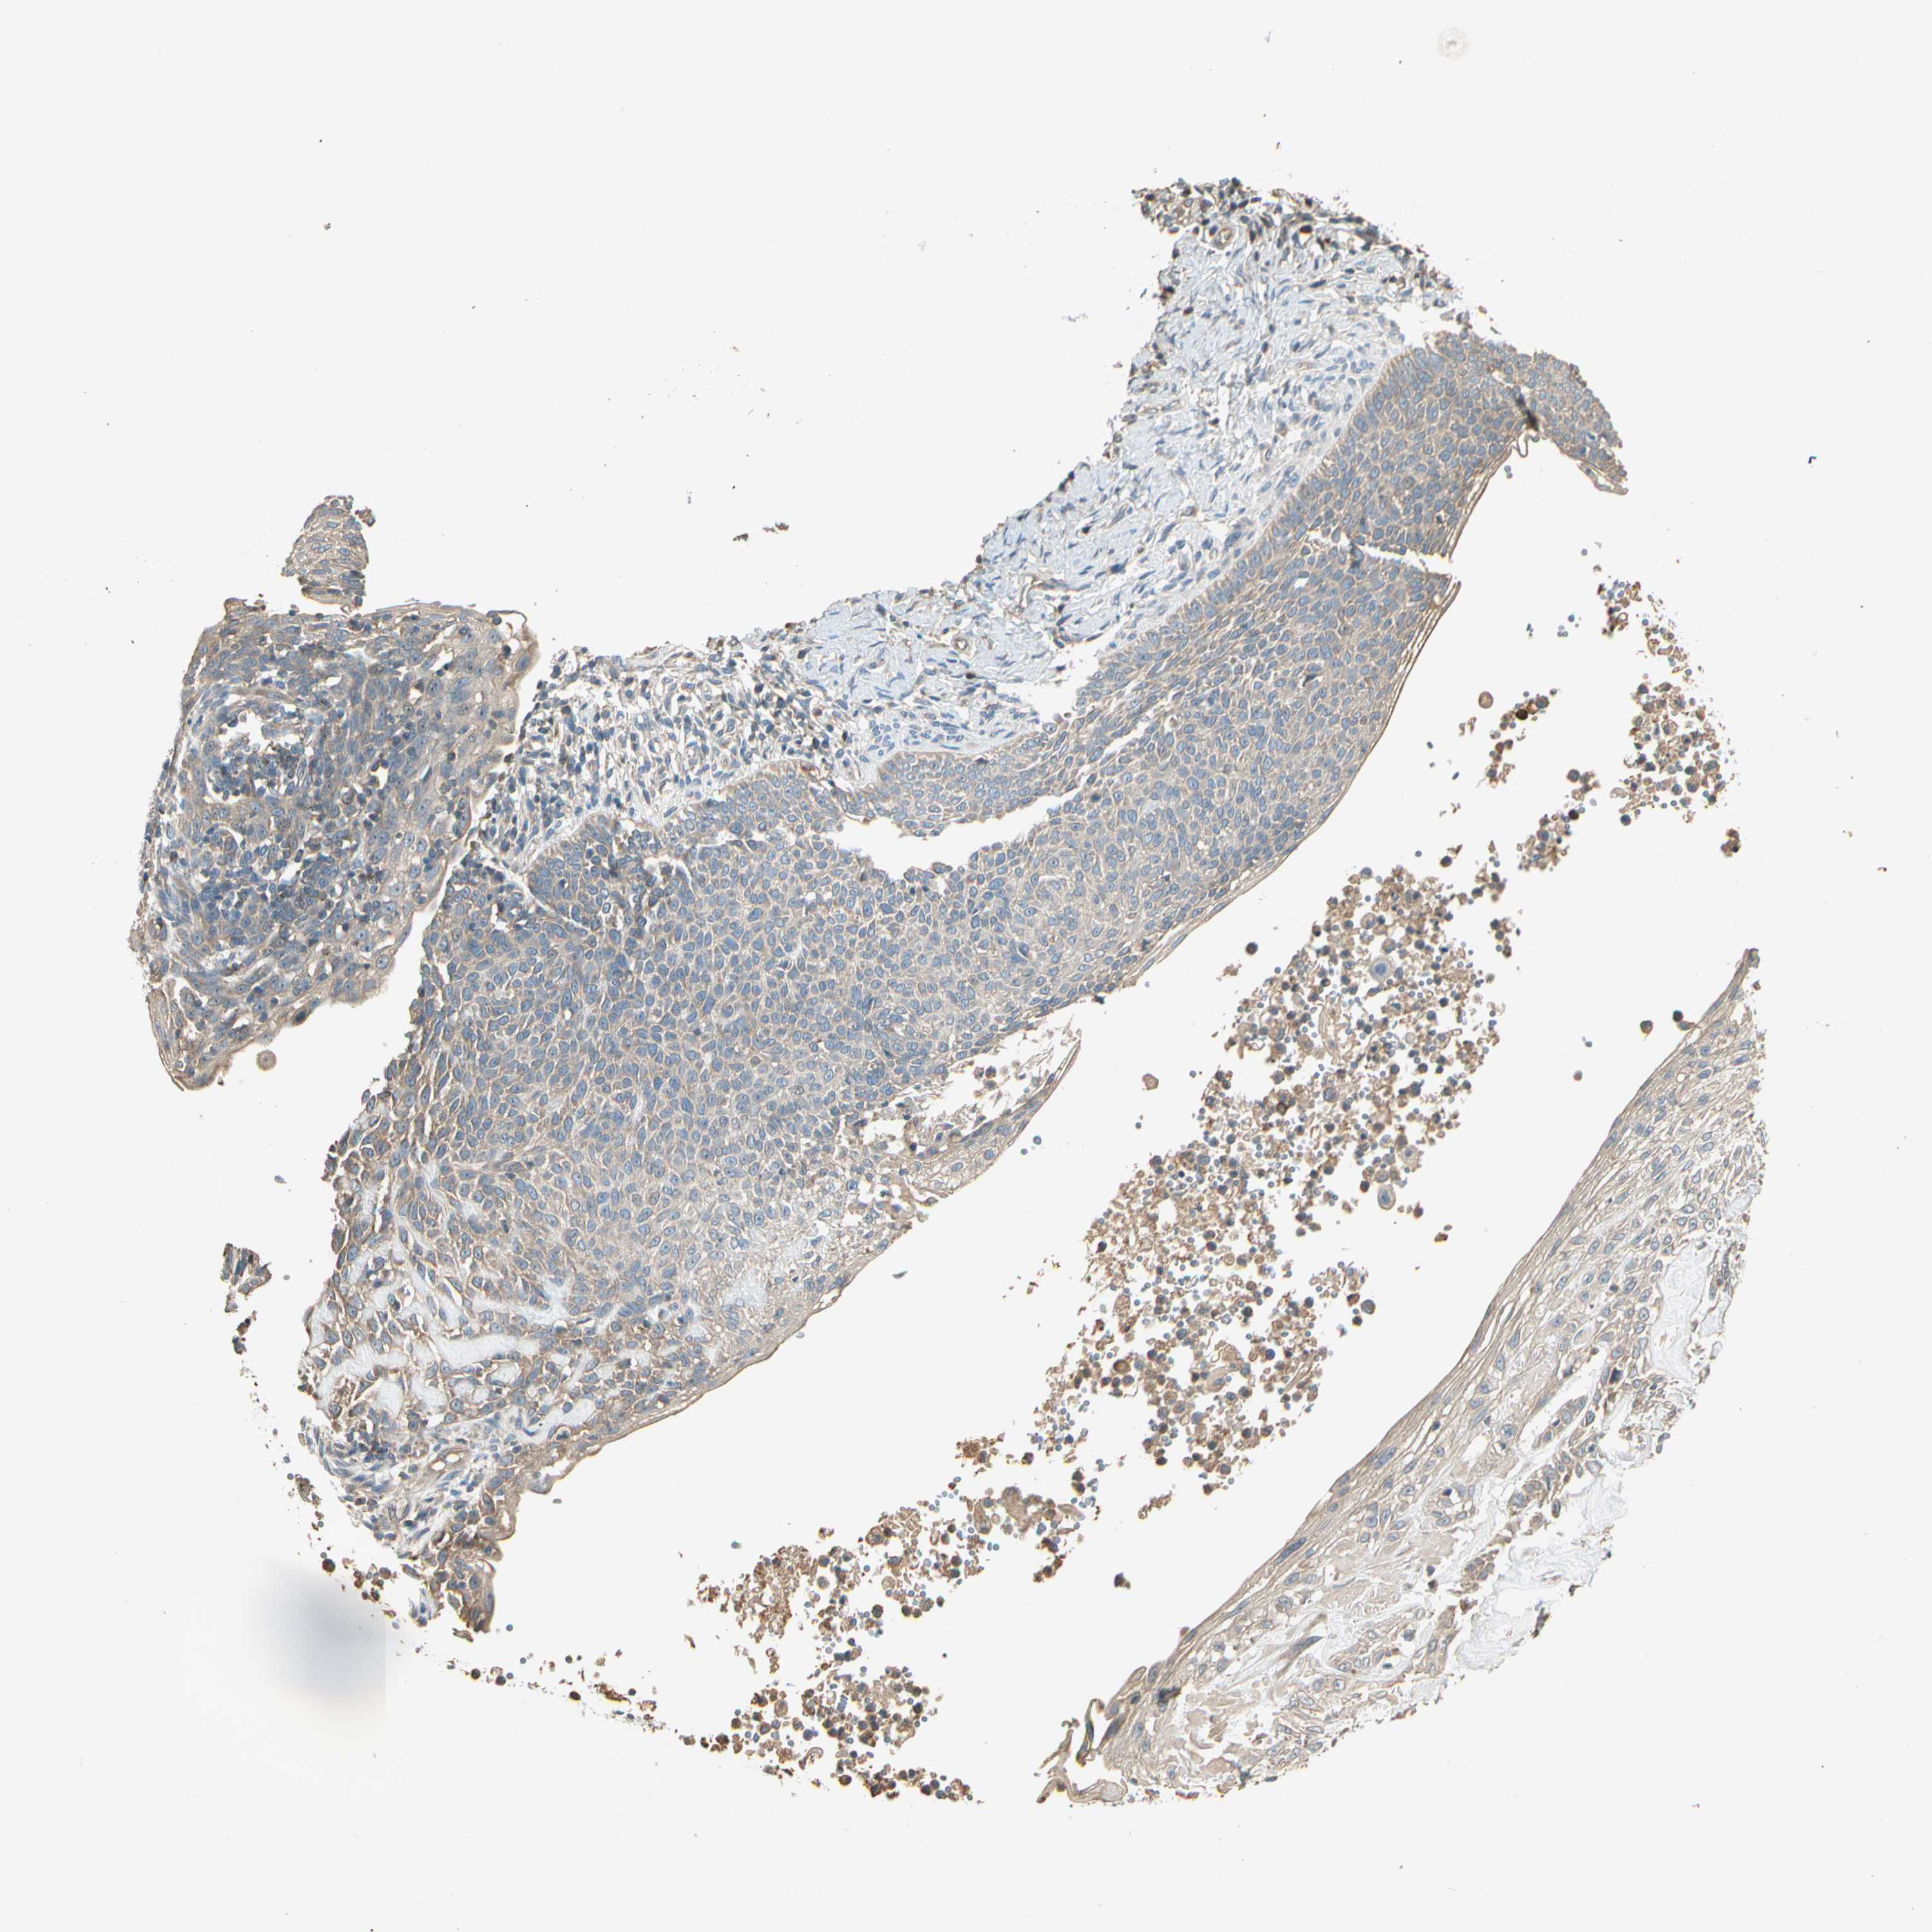

SKIN CANCER - Protein expressioni

A mouse-over function shows sample information and annotation data. Click on an image to view it in a full screen mode. Samples can be filtered based on level of antibody staining by selecting one or several of the following categories: high, medium, low and not detected. The assay and annotation is described here.

Antibody stainingi

Antibody staining in the annotated cell types in the current human tissue is reported as not detected, low, medium, or high, based on conventional immunohistochemistry profiling in selected tissues. This score is based on the combination of the staining intensity and fraction of stained cells.

Each image is clickable and will lead to virtual microscopy that enables deeper exploration of all samples and also displays staining intensity scores, fraction scores and subcellular localization as well as patient and tissue information for each sample.

Antibody HPA006746

Antibody CAB009805

Squamous cell carcinoma, NOS

Squamous cell carcinoma, metastatic, NOS